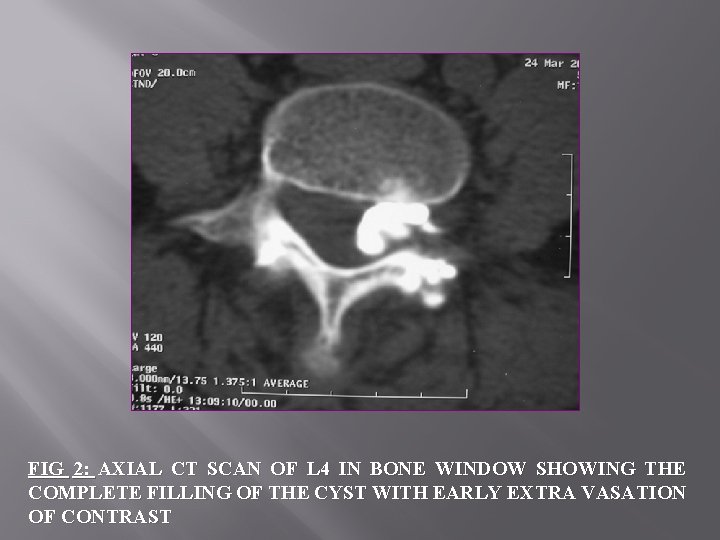

FIG 2: AXIAL CT SCAN OF L 4 IN BONE WINDOW SHOWING THE COMPLETE FILLING OF THE CYST WITH EARLY EXTRA VASATION OF CONTRAST

2/ PROGRESS OF INTERVENTIONAL GESTURE: üAfter local anesthesia and surgical skin disinfection üJoint aspiration and injection of 1 ml of iodinated contrast in facet joint, opacified both the joint and the cyst intra canal, objectifying the communication between them. üfluid üThen content was aspirated we have inject a bulb of a prolonged action corticosteroid (Altim®) combined with 1 cc of Xylocaine® under pressure until rupture of the cyst, as evidenced by a loss of strength and opacification of the epidural space on the acquisition of control.